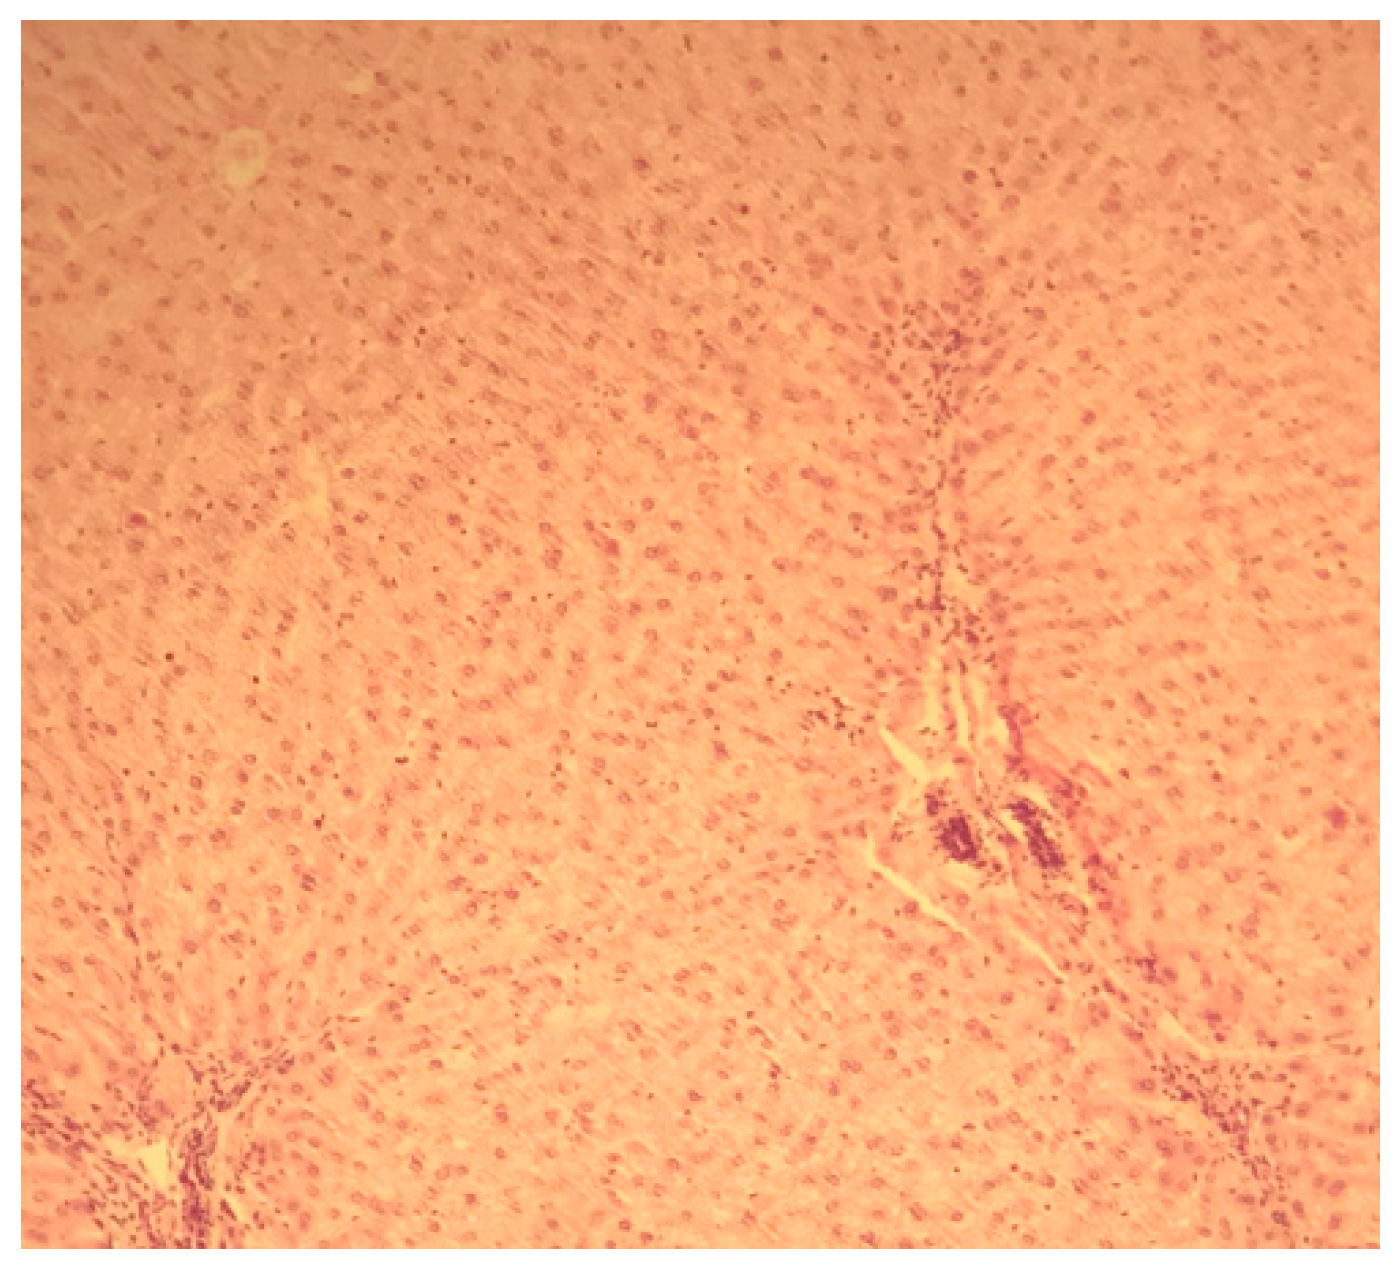

Figure 1. Liver H&E staining x10.